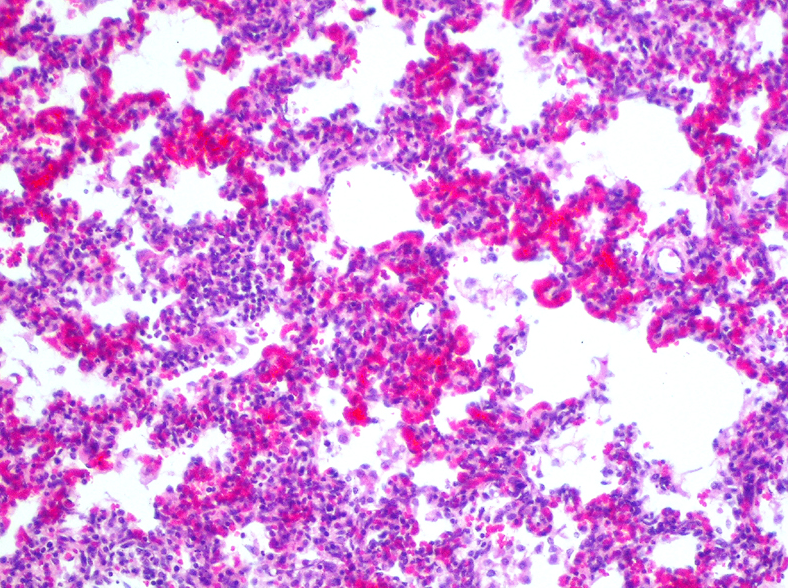

Identify

and

provide Microscopy of this slide:

Interstitial pneumonia

Identify slide:

Give 4 examples:

Type 1 – most sensitive to damage and loss of integrity (intra-alveolar)

4 types:

identify: